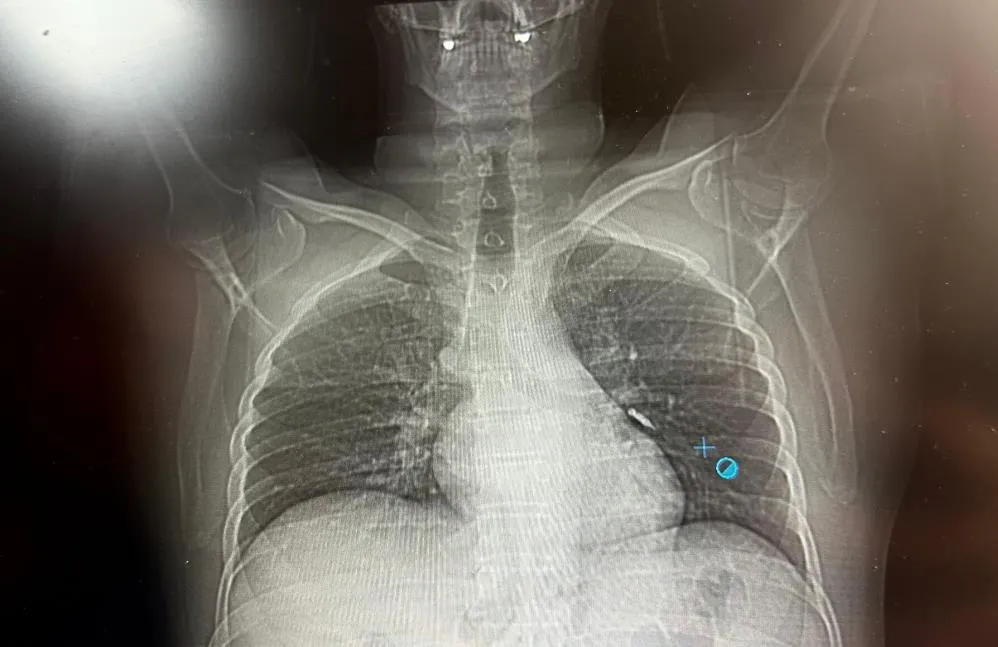

Konuya ilişkin konuşan Göğüs Cerrahi Op. Dr. Sadullah Aksoy, bir diş merkezinde diş tedavisi sırasında hastanın çenesine yerleştirilen implantın vida kısmının işlem esnasında yanlışlıkla aspire edildiğini belirtti. İlk olarak hastanenin ek hizmet binasında çekilen tomografi sonucunda, vidanın sol akciğerin hava yollarının yaklaşık dördüncü dalına kadar ilerlediği tespit edildiğini ifade eden Op. Dr. Aksoy, "Geçtiğimiz cumartesi günü öğle saatlerinde tarafımıza ulaşıldığında, hastanın Van Eğitim ve Araştırma Hastanesi'ne yönlendirilmesini istedik. Burada acil bronkoskopi planı yapılarak hasta kabul edildi. Hasta geldiğinde genel durumu iyiydi; solunumunu tamamen engelleyen bir bronş tıkanıklığı söz konusu değildi. Aynı gün hastamızı hazırladık. Bronkoskopi sırasında, implant vidasının sol üst lobun anterior segment bronşuna saplanmış pozisyonda olduğunu gördük. Üroloji bölümünde taş çıkarma işlemlerinde kullanılan cihazla müdahale ettik. İlk denemede implant tamamen çıkarılamadı ancak yerinden oynatılabildi. Bunun üzerine bir süre bekleyip hastayı yeniden bronkoskopi için hazırlamaya başladık. İşlem yaklaşık 3,5-4 saat sürdü ve saat 18.30 civarında hasta işlemden çıkarıldı" dedi.

Daha sonra hasta için yeniden bronkoskopi planladıklarını ancak bu süreçte hasta şiddetli bir öksürük geçirdiğini anlatan Aksoy, "Şiddetli öksürük sonrası yapılan kontrol akciğer filminde implant vidası görünmedi. Bunun üzerine toraks ve batın BT (bilgisayarlı tomografi) görüntülemesi istedik. Sonuçlarda implantın akciğerden çıktığı ve vücutta herhangi bir yerde bulunmadığı tespit edildi" diye konuştu.